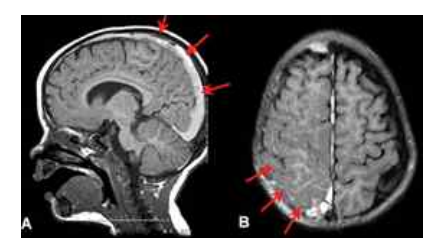

아래 그림이 거미막밑출혈(지주막하출혈) 시 볼 수 있는 영상 촬영 사진이다.

빨간색 화살표 부분에 하얗게 고인 것이, 출혈로 생기는 진한 선에 피라고 생각하면 이해하기 쉬울 것이다.